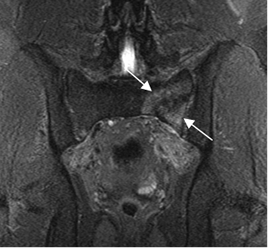

Fig 75. Fractura de stress.

A: RM coronal en T1 y B: RM coronal en STIR. Igual paciente anterior. También existe fractura no desplazada, en el ramo iliopúbico derecho. (Flechas).